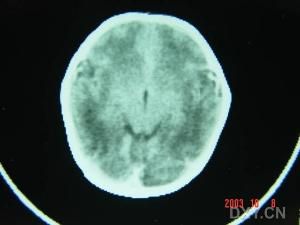

1.頭顱CT或MRI檢查影像檢查目的是進一步明確HIE病變的部位和範圍,確定有無顱內出血和出血類型,動態系列檢查對評估預後有一定意義。由於生後病變繼續進展,不同病程階段影像檢查所見會有不同。通常生後3天內以腦水腫為主,也可檢查有無顱內出血,如要檢查腦實質缺氧缺血性損害或腦室內出血,則以生後5~10天為宜,3~4周后複查,有助於判斷永久性腦損害。(1)CT檢查新生兒HIE行CT掃描時要測定腦實質的CT值(單位為Hu),正常足月兒腦白質CT值在20以上,18為低密度。要排除與新生兒腦發育有關的正常低密度現象,即在早產兒的額、枕區和足月兒的額區呈低密度為正常表現。HIE的CT分度標準:輕度:散在、局灶白質低密度影,分布2個腦葉。中度:白質低密度影超過2個腦葉,白質灰質對比模糊。重度:瀰漫性白質低密度影,灰質白質界限消失,但基底節、小腦尚有正常密度。雙側大腦半球呈瀰漫性低密度影,腦室變窄甚至消失,提示存在腦水腫。雙側基底神經節和丘腦呈對稱性密度增高,提示存在基底神經節丘腦損傷。在大動脈分布區見單側腦組織密度降低,提示存在大腦大動脈及分支的梗塞。在腦室周圍尤其側腦室前角外上方呈對稱性低密度影,提示為腦室周圍白質軟化,常伴有腦室內出血。中、重度HIE60%~70%合併蛛網膜下腔出血(SAH)。而成人重症HIE患者發病後2~4h內部分頭顱CT未見異常,可能與CT在早期不敏感有關。(2)MRI檢查新生兒HIE的MRI早期表現有廣泛腦水腫、顱內出血、皮質下及腦室旁白質損害、丘腦及基底節區和腦幹背側異常信號等同;晚期可表現為腦室周圍腦白質軟化症、分水嶺區腦損傷等同。而成人HIE早期(10天內)MRI可表現為腦水腫、灰白質分界消失、大腦皮質層層狀壞死、顱內出血;晚期(10天~6個月)可表現為皮層下白質及深部白質脫髓鞘改變、選擇性神經元壞死、廣泛腦損害、腦萎縮。2.頭顱B型超聲(B超)檢查以嬰兒前囪為窗,作冠狀面和矢狀面扇形超聲檢查。可在床旁操作,無射線影響,還可多次追蹤檢查,優點較多。對腦水腫、腦實質病變和腦室增大顯示清楚。新生兒HIE的頭顱B超檢查發現:①腦實質內廣泛均勻分布的輕度回聲增強,伴腦室、腦溝及半球裂隙變窄或消失,及腦動脈搏動減弱,提示存在腦水腫。②基底神經節和丘腦呈雙側對稱性強回聲反射,提示存在基底神經節和丘腦損傷,常與腦水腫並存。③在腦動脈分布區見局限性強回聲反射,提示存在大腦大動脈及其分支的梗塞,多為單側,尤以左側多見。④在冠狀切面中,見側腦室前角外上方呈倒三角形雙側對稱性強回聲區;在矢狀切面中沿側腦室外上方呈不規則分布強回聲區,提示存在腦室周圍白質軟化,常與腦室內出血並存。3.腦電圖檢查新生兒HIE腦電圖波形特點是低電壓、等電位和爆發抑制波。腦電圖輕度異常表現為背景節律呈持續性5~25LV低電壓的D波,無正常足月兒腦電圖常見的在D波上重疊的快H波和A波。中度異常是在抑制背景上爆發高電壓波,波幅可高達180LV,抑制時間持續2~4秒。重度異常中爆發波降至50LV左右,抑制時間持續20~97秒,抑制背景為波幅0~5LV的等電位或波幅5~15LV的低電壓。HIE腦電圖檢查異常程度與臨床分度基本一致,故一周內腦電圖可用來判斷HIE病情輕重。當臨床症狀因受藥物或其他病理因素影響而不易判斷時,腦電圖對判斷病情輕重和臨床分度更有價值。腦電圖對判斷預後也有參考價值,當患者治療二周后,臨床症狀雖有好轉,而腦電圖尚未完全恢復,仍有等電位、低電壓或爆發抑制波,提示腦神經細胞的功能尚未完全恢復,仍應繼續治療,否則會影響預後。4.血清酶活性測定新生兒窒息後可引起多臟器功能損害,大量酶類自損傷細胞逸出至血液。一般認為窒息嬰兒血清中CPK、LDH和AST活性只能表明窒息程度,不能真實反映心肌細胞或腦細胞損傷程度。國外文獻報導,血清中CPK、LDH、AST活性與HIE的病情輕重無關,不能作為診斷和臨床分度的依據,但高到一定程度與預後有關,即預後不良患者血清酶活性較預後正常患者顯著增高,可作為早期預報預後的依據。但有學者報導如CPK活性>2000U/L,LDH>900U/L,AST>150U/L,提示預後不良可能性較大。血清酶活性的半衰期很短,在24小時內達到高峰,應在生後1天內採血測定其活性。CPK的腦型同功酶(CK-BB)主要存在於腦部神經細胞和星形膠質細胞中,腦損傷時從細胞內釋放出來,有較大特異性,其測定有助於HIE的病情嚴重程度判斷和早期預報預後。5.腦脊液檢查為減少對患兒的擾動,應避免作腦脊液檢查,只有在需要排除化膿性腦膜炎時才作這項檢查。值得注意的是正常新生兒腦脊液可能有極少量紅細胞進入腦脊液,或因黃疸使腦脊液呈淡黃色。並不表示有顱出血。